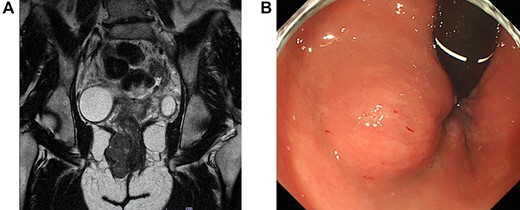

A 43-year-old female underwent pelvic magnetic resonance imaging (MRI) for uterine myoma that incidentally revealed a 4.6 × 2.8 cm soft tissue mass in the right perineal area (Fig. 1A). Rectal endoscopy showed a submucosal tumor just above the anal canal (Fig. 1B). FDG-PET/CT scan revealed an anorectal tumor with very high 18F-FDG uptake (SUVmax = 17.9; Fig. 2). As aspiration cytology and needle biopsy were inconclusive, we planned to perform trans-perianal tumor resection.

(A) Magnetic resonance imaging of the pelvis (sagittal section) demonstrates a 4.6 × 2.8-cm tumor in the right perineal area. (B) Proctoscopy reveals a submucosal tumor near the right wall of the anal canal.